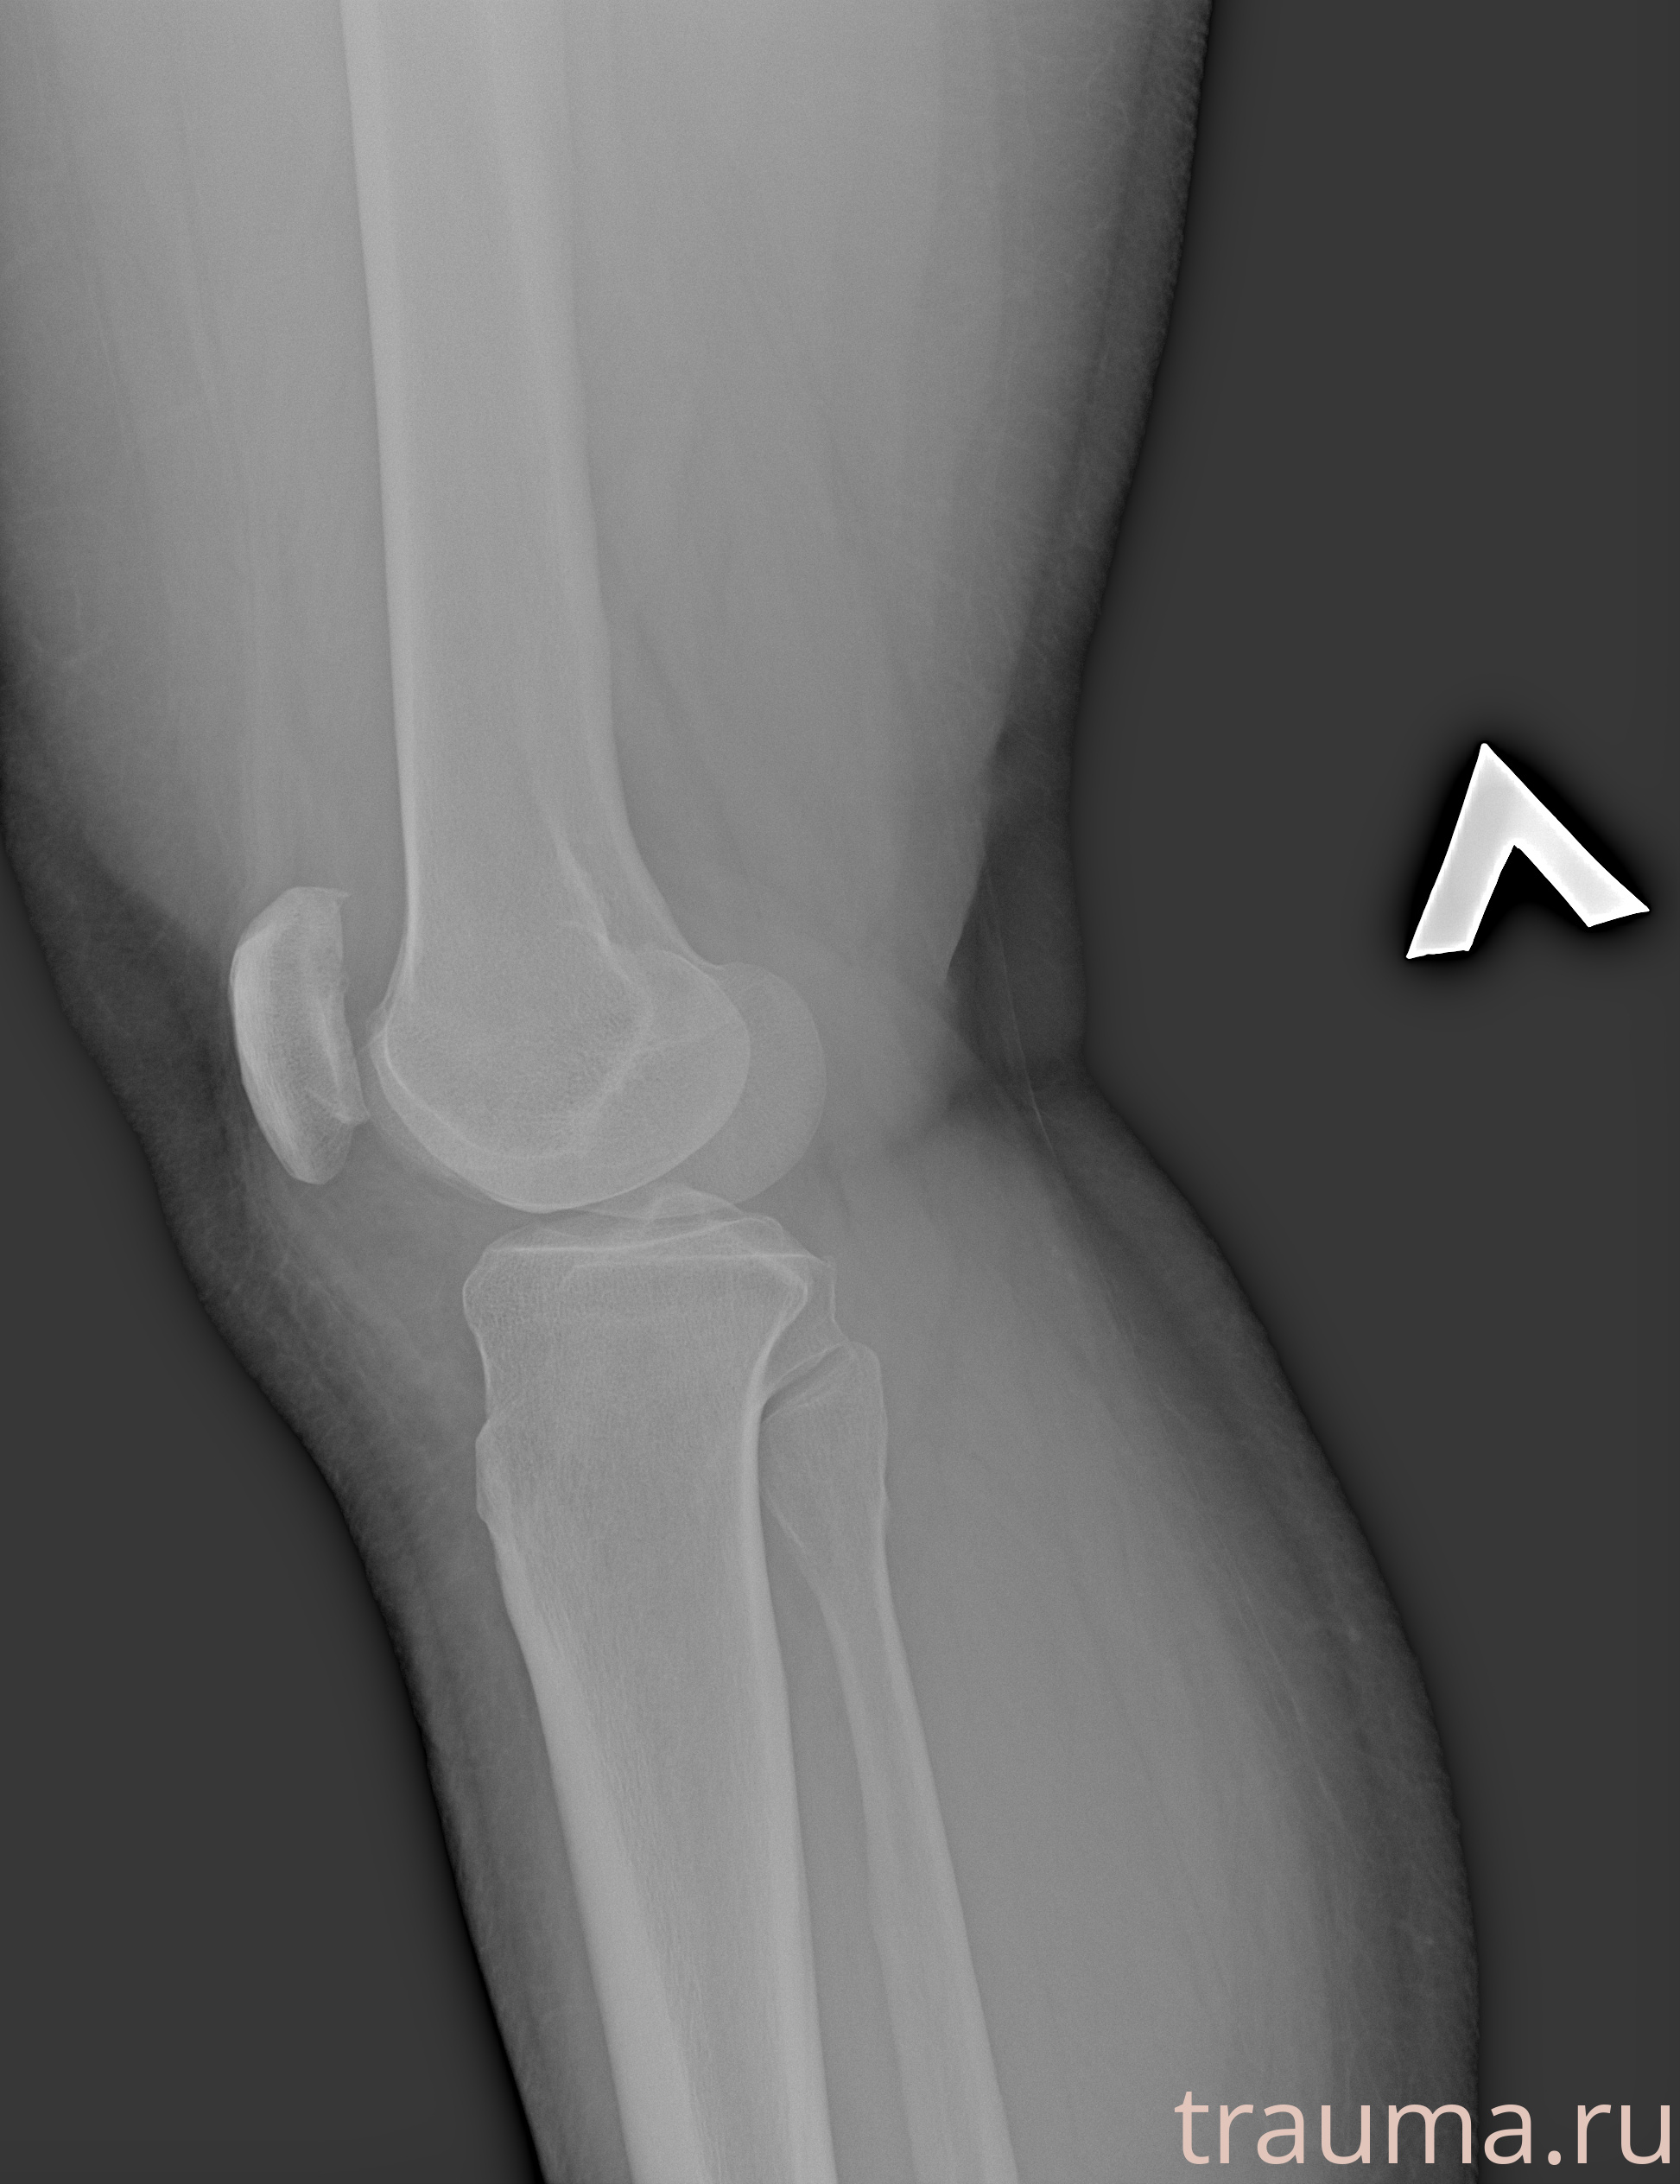

Рентгенограммы

Рентген на дому: по вашему адресу приезжает врач-рентгенолог, травматолог-ортопед с мобильным рентгеновским аппаратом, проводит диагностику травмы или заболевания, делает необходимые рентгенограммы, дает рекомендации по дальнейшему лечению. Получить качественные снимки в домашних условиях возможно благодаря уникальной методике, разработанной МосРентген Центром для института  Склифосовского